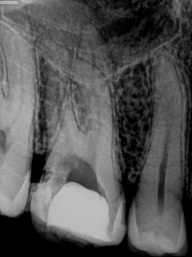

Atualmente são várias as técnicas para a remoção de instrumentos fraturados no canal, e é fundamental que o Endodontista conheça todas elas, pois cada caso uma determinada técnica pode funcionar em detrimento das outras.

Na remoção de qualquer tipo de instrumento fraturado no canal é muito importante primeiramente o domínio da técnica empregada para removê-lo, ter todos os equipamentos em mãos, sendo fundamental o microscópio operatório e ultrassom com pontas especificas para o trabalho em questão.

O Microscópio favorece a obtenção de sucesso na remoção de instrumentos fraturados dentro do canal pois amplifica o campo de visão, aumenta a luminosidade proporcionando precisão no trabalho do profissional, evitando desgastes excessivos na raiz e até mesmo uma perfuração e perda do dente, o uso desse equipamento é fundamental para sucesso do trabalho.

O segundo equipamento mais importante é o Ultrassom, com uma grande eficiência na remoção de instrumentos fraturados dentro do canal, desde que o profissional consiga posiciona- lo corretamente em cada caso de fratura específico, a fim de direcionar corretamente a pota ultrassônica sobre o instrumento fraturado.